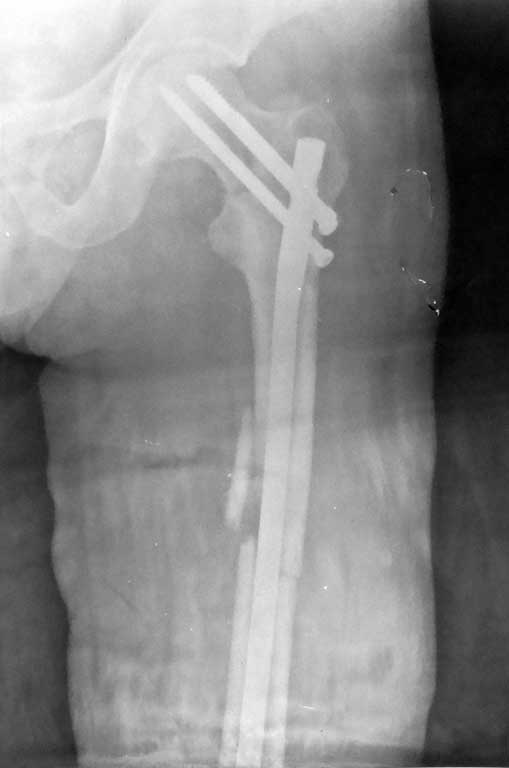

Уважаемые коллеги, на форуме был представлен случай перелома шейки и диафиза бедра, где после БИОС наступил варус шейки и винты упирались в крышу сустава.

Форумом было рекомендовано пересинтезировать. Мы пригласили нашего дорогого друга Челнокова А.Н., основоположника БИОС в нашем регионе, который несмотря на очень занятость, и дальность расстояния решил выручать коллег, и приехал к нам. Уже прошло 2 мес. после первой операции. Винты из шейки удалены, наложен дистрактор, произведена закрытая репозиция шейки, стержень ChM удален, произведен остеосинтез стержнем DePuy, шейка фиксирована, кроме стандартных двух винтов, еще одним винтом спереди стержня. рентген снимки прилагаются.

Имя     : forum AP view.jpg